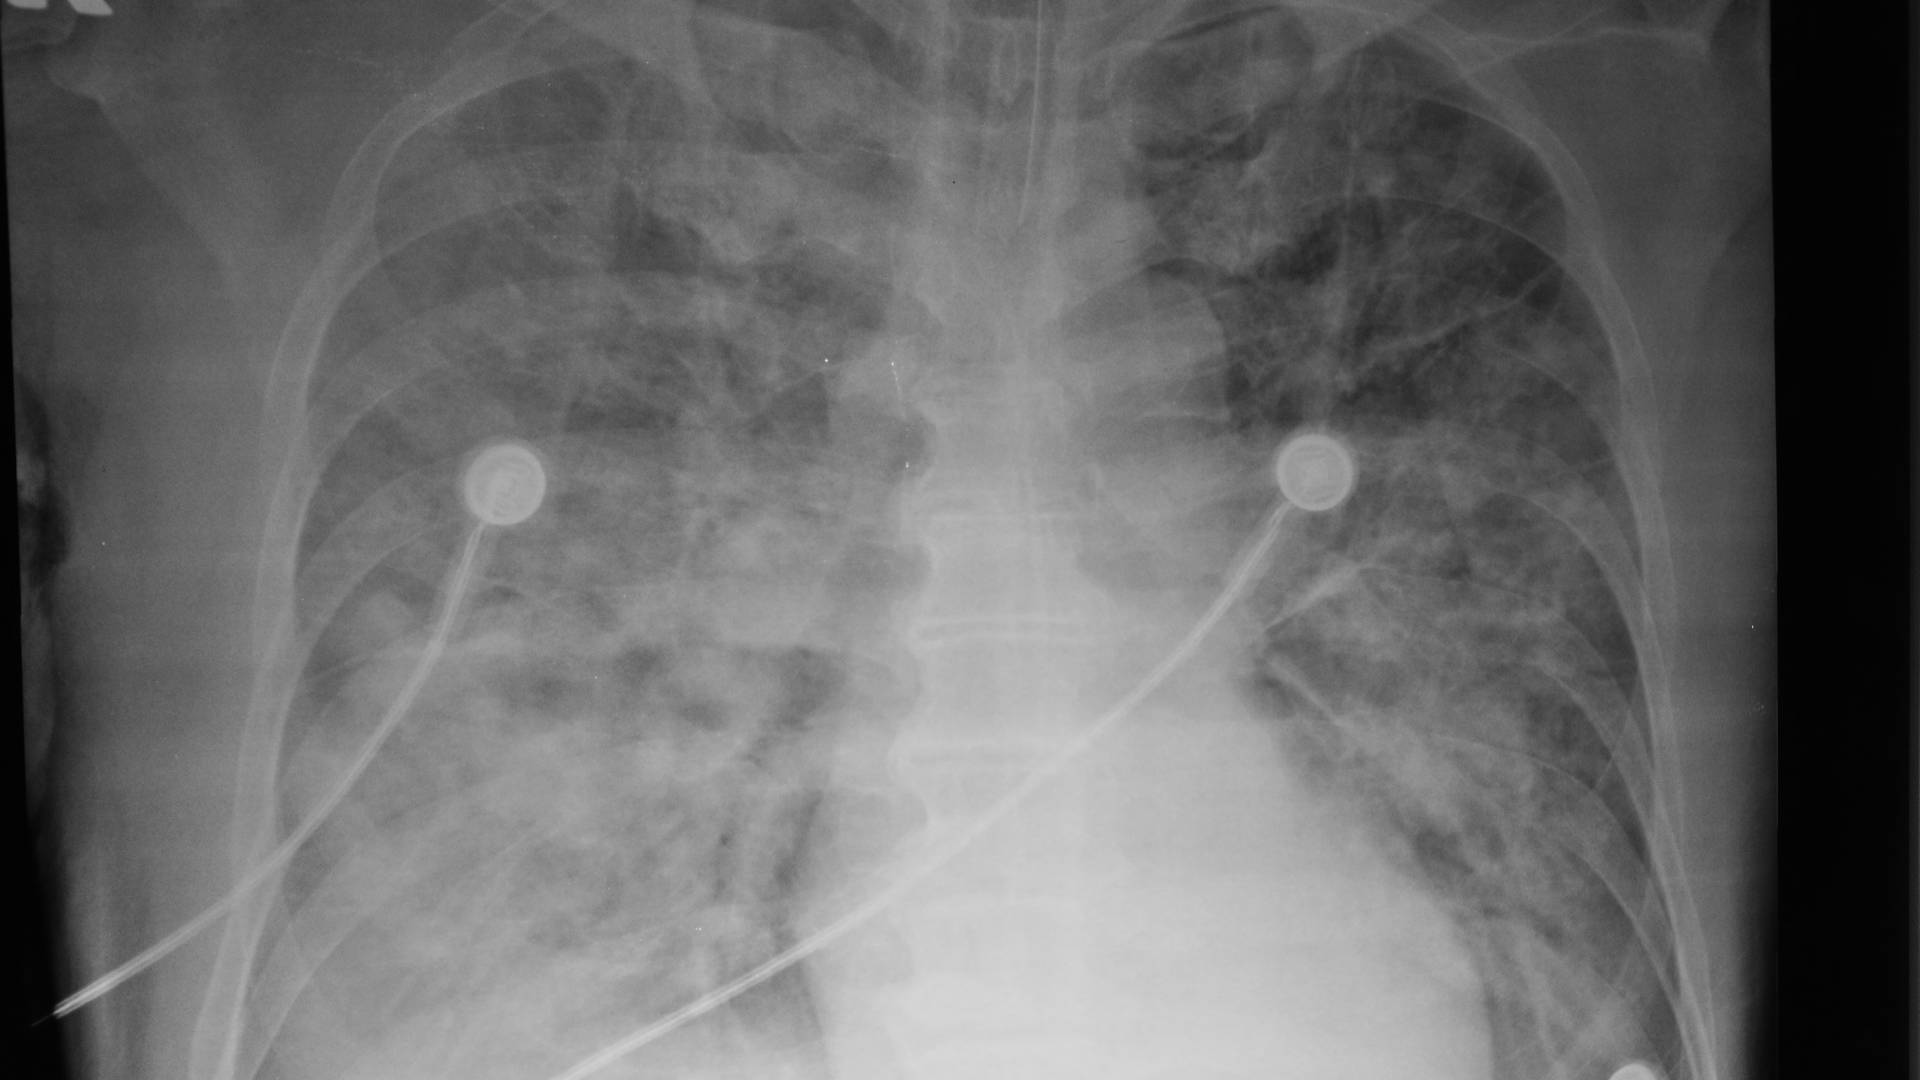

• Adults with acute lung injury (ALI) or ARDS, defined by PaO₂/FiO₂ ≤300 for ALI and ≤200 for ARDS, onset within 36 hours

• Bilateral pulmonary infiltrates on chest imaging not primarily due to left atrial hypertension